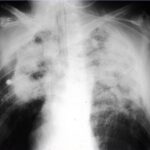

Una enfermedad que avanza con rapidez devastadora

Los casos como el de Marek Marzec ponen de manifiesto la velocidad con la que puede deteriorarse la salud de una persona tras inhalar partículas de sílice liberadas al trabajar encimeras de piedra artificial. En su caso, falleció apenas siete meses después de recibir el diagnóstico de silicosis, un curso clínico que coincide con los patrones descritos en publicaciones científicas internacionales sobre silicosis de progresión rápida en trabajadores de piedra artificial.